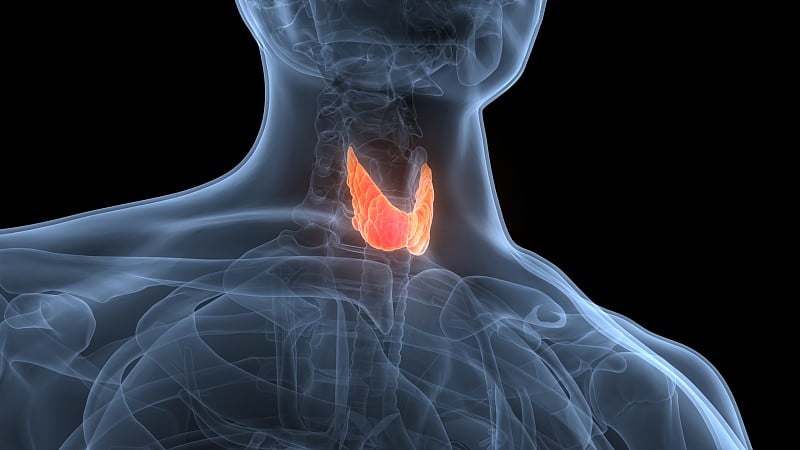

人体腺体甲状腺解剖学详情

JPG

人体腺体甲状腺解剖学详情

JPG